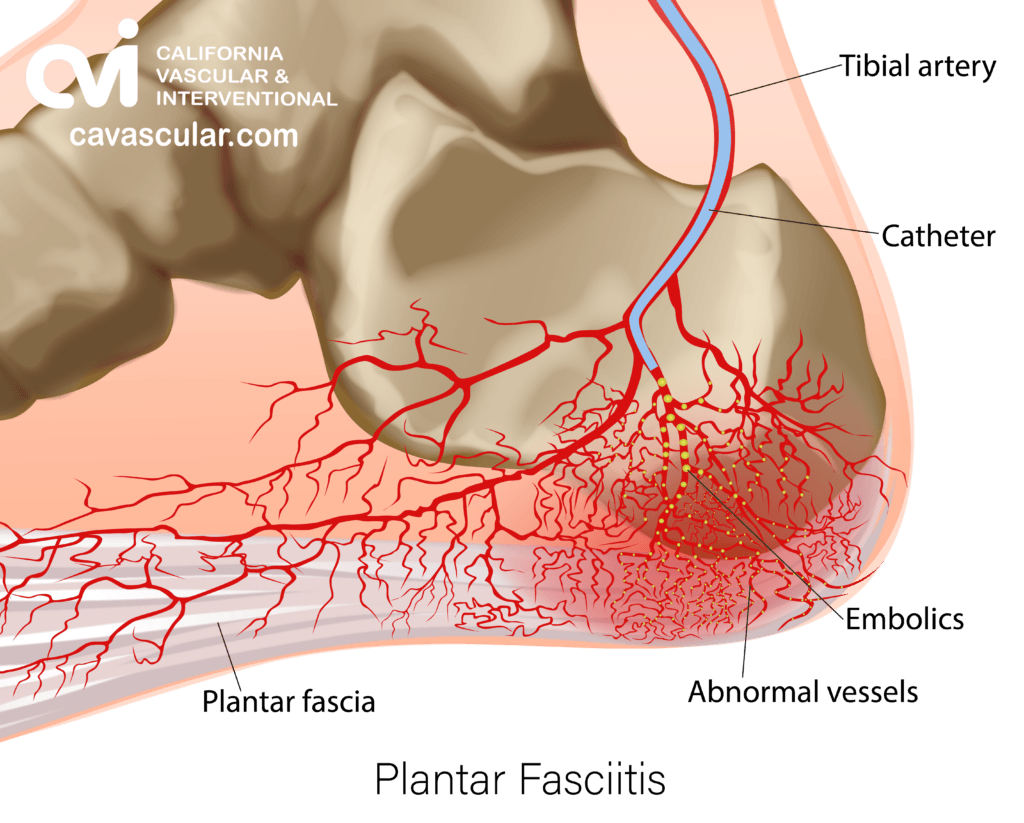

In cases of chronic plantar fasciitis, researchers have observed an increase in abnormal neovascularization (the growth of new blood vessels) around the inflamed plantar fascia. These new blood vessels are believed to contribute to the chronic inflammation and persistent pain associated with the condition. Embolization works by blocking these abnormal blood vessels, thereby reducing blood flow to the inflamed tissue, which in turn decreases inflammation and promotes healing.

Plantar Fasciitis Embolization (PFE) is performed by our double board-certified interventional radiologist under local anesthesia.

After a small numbing injection, a tiny “IV like” catheter is inserted into the blood vessel at the ankle, using real-time ultrasound and sometimes x-ray imaging. Once the catheter is in position, tiny embolic antibiotic agents are introduced into the blood vessels to block the abnormal vessels. The embolic agents cut off the blood supply to the abnormal vessels but leave normal vessels intact, reducing inflammation and pain in the affected area.